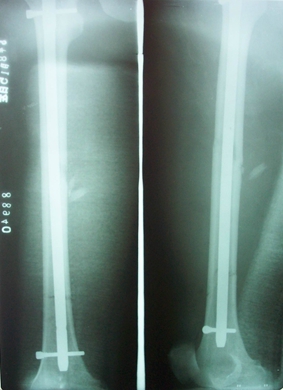

图5. 股骨干多段骨折

图6. 股骨干多段骨折带锁髓内钉内固定术后